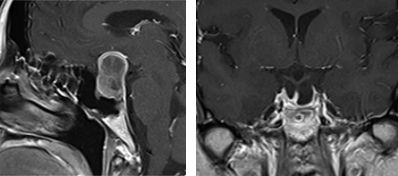

下垂体腺腫内視鏡単独経鼻的アプローチ

下垂体腺腫に対して内視鏡単独で経鼻的アプローチにより摘出術を施行。耳鼻科医と合同で行っている。(左)術中および術後MRIの所見。腫瘍被膜上に造影病変が認められているが、術後MRIでは消失している。術中MRI画像をナビゲーション用にアップデートし、残存腫瘍の摘出操作の際に役立てている。